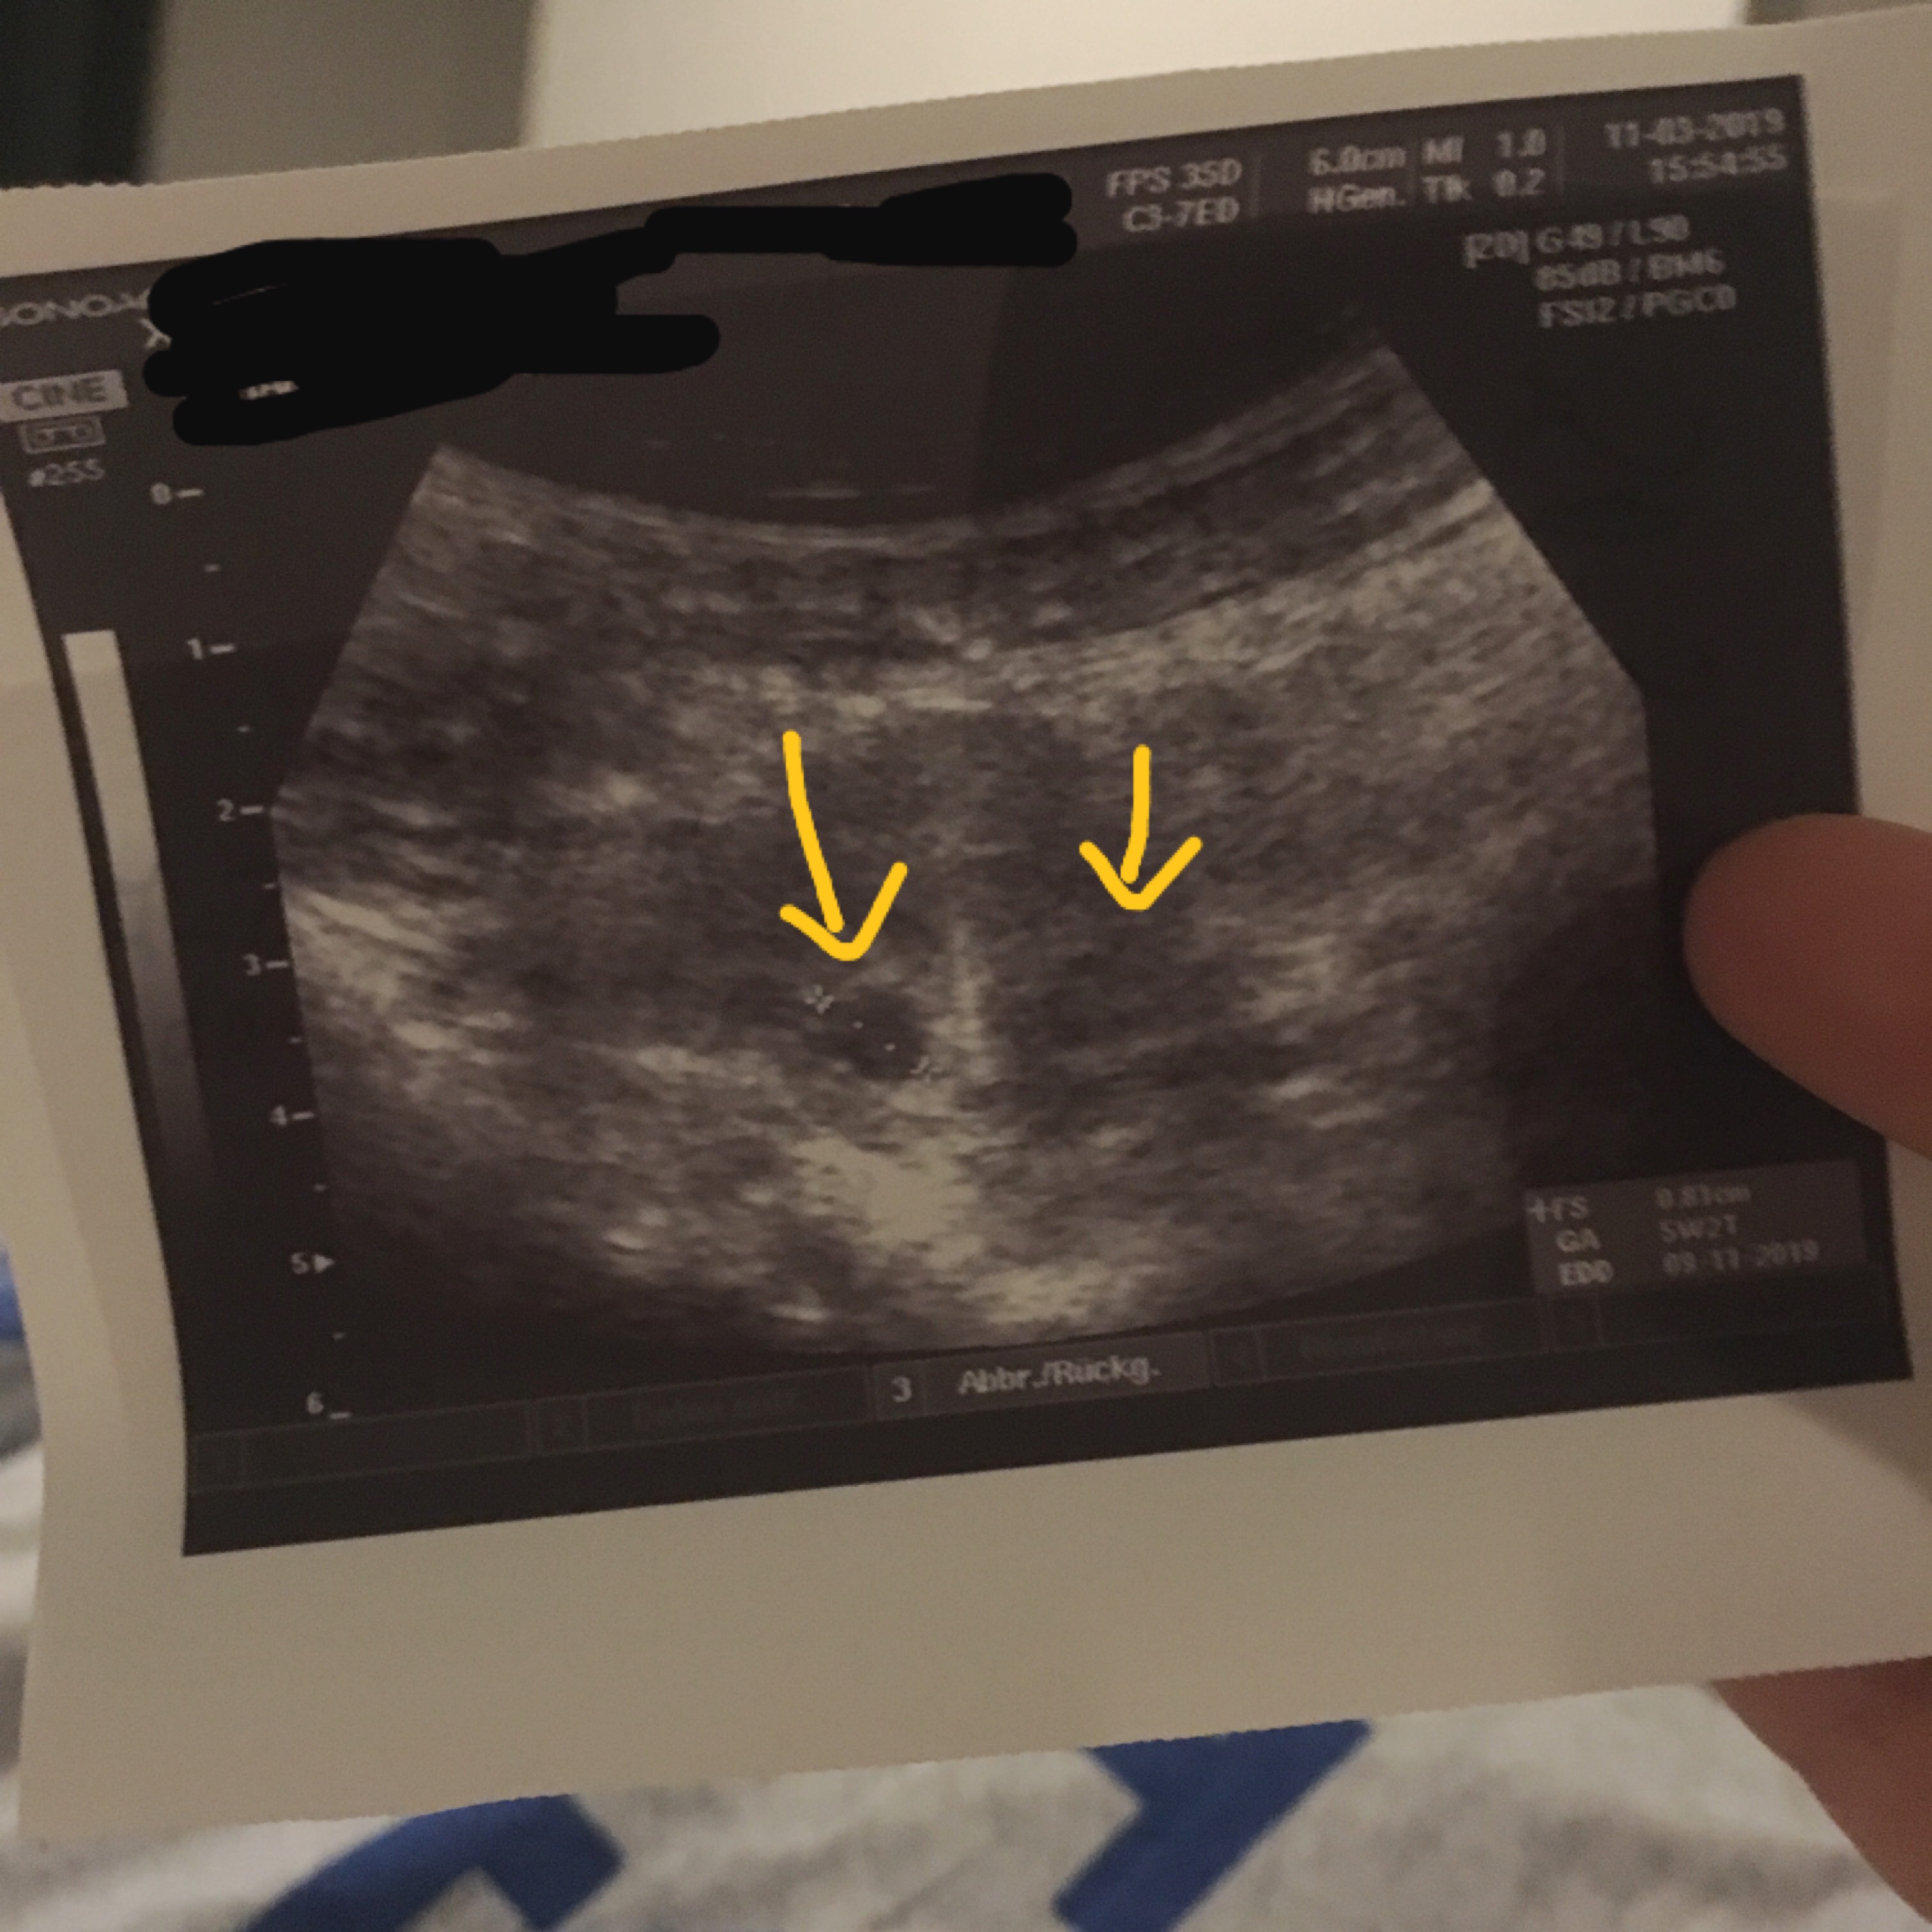

Und am 116 hatte ich einen positiven SSW Test Ich war dann auch gleich beim FA am 116 und er sah eine kleine Höhle von 0,33cm, Montag den 146 war ich wieder beim FA und er sah wieder eine Höhle von 0,70cm So, nun EINE WOCHE später, heute war ich wieder beim FA und wieder sah er nur die Fruchthöhle mit 0,94cm und aber. Bei mir hat man in der 5 Woche auch noch keine Fruchthöhle gesehen, nur die aufgebaute Gebärmutterschleimhaut und später ist dann raus gekommen, dass ich doch erst in der 4 Woche war und deshalb auf dem Ultraschall noch nichts zu sehen war!. SSW 60 nur Fruchthöhle, kein Embryo, kein Dottersack Maroni2701 schrieb am 1651 Registriert seit Beiträge 21 Hallo, ich bin im Moment sehr traurig Zuerst mag ich aber meinen Verlauf erzählen war mein erster der letzten Periode genau zwei Wochen danach hat der Clearblue Test angezeigt.

6 ssw kein embryo nur fruchthöhle und dottersack Fruchthöhle mit Dottersack, aber kein Embryo Auf dem durchgeführten Ultraschall zeigte sich erneut die Fruchthöhle, mit Dottersack, aber war von der Größe her nur einen Millimeter (auf 8,8mm) angewachsen, was der 5W5T entsprechen würde. Ich habe eine frage ich bin das zweite mal schwanger und jetzt aktuell bei 61 sprich 7 Ssw Ich hatte vergangenes Wochenende ein grosses Hämatom neben der Fruchthöhle was abgeblutet ist hörte nach 48 std vollkommen auf zu bluten Auf dem bild 55 sah man nur eine Fruchthöhle Genau wie gestern bei 60 Nur eine 9mm grosse Fruchthöhle. 6 Schwangerschaftswoche (6 SSW) Alles zur Entwicklung des Babys in Ihrem Bauch, Ultraschall, Herzschlag, Symptomen und Anzeichen sowie Videos zur 6 SSW.

Ich habe eine frage ich bin das zweite mal schwanger und jetzt aktuell bei 61 sprich 7 Ssw Ich hatte vergangenes Wochenende ein grosses Hämatom neben der Fruchthöhle was abgeblutet ist hörte nach 48 std vollkommen auf zu bluten Auf dem bild 55 sah man nur eine Fruchthöhle Genau wie gestern bei 60 Nur eine 9mm grosse Fruchthöhle. 66 SSW, nur Fruchthöhle und Dottersack da Hallo ihr Lieben, wie meine Frage schon sagt, hatte ich in der 66 SSW ein Termin zum Ultraschall und man hat nur die Fruchhöhle mit Dottersack gesehen Eine Woche zuvor hat man nur die Fruchthöhle gesehen. Fruchthöhle in der 61 ssw nur 2mm gross ist das normal?Bitte bitte antwortet mir Musste dann in der praxis nochmal nen ss Test machen,der war immernoch PositivSie hat dann nen Ultraschall aufm Bauch gemacht und nach ewig langem suchen hat sie ENDLICH die Fruchthöhle gefundenaberich sag Dirsoooo winzig!).